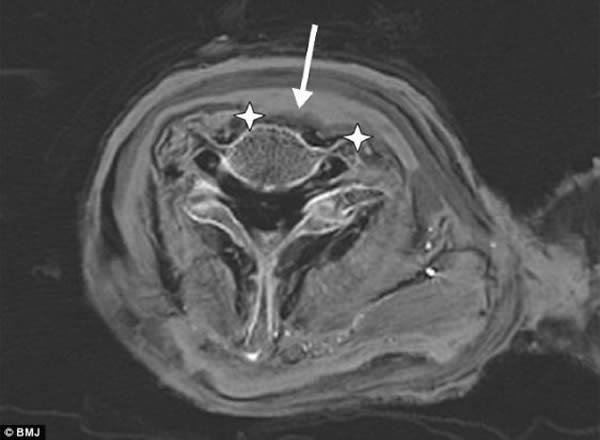

拉美西斯三世的颈部轴向CT剖面图:星迹指示的是他脖子上一道2.7英寸(6.86厘米)伤口的边缘处,箭头指向已经渗入伤口的防腐材料

刊登在《英国医学杂志》上的研究论文指出,经过对拉姆西斯三世的木乃伊进行CT扫描,研究人员发现喉咙处存在一个深深的切口,可能由一把锋利的匕首造成。这场暗杀行动在一场皇室政变时进行。研究论文称:“我们的CT扫描发现了拉姆西斯三世遭人割喉的证据。”CT扫描显示,拉姆西斯三世的喉咙、颈部和动脉均被割断,立时毙命。

研究人员表示:“喉咙不可能在死后遭受损伤,因为在1886年打开拉姆西斯三世木乃伊时,其颈部衣领完好无损,没有遭受一点损伤。当时,人们用锤子从这具木乃伊身上敲掉一层厚厚的沥青。证明遭人暗杀致死的进一步证据是,伤口处发现了霍鲁斯(古埃及的太阳神)之眼护身符。这个护身符位于软组织深处,穿过利器造成的伤口,直达骨头。护身符的发现证明在制作木乃伊前这个伤口就已存在。”